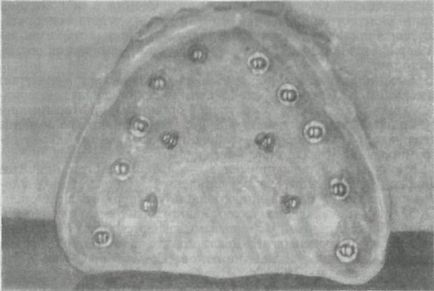

Ábra. 277. submucosalis implantátumok teljes fogsor felső állkapocs.

1. intramucosalis implantátumok (nyálkahártya alatti). Intramucosalis implantáció javítására használják rögzítéséhez protézis atrophia alveoláris csont a maxilla, különösen, ha hibák szájpad fejlődését. Az implantátum egy kétoldalas cap, amelyek közül az egyik mereven van rögzítve a bázis a lemez kivehető fogpótlás, a másik rész (gomba alakú) vezetünk be a létrehozott (anesztézia alatt) kerek fúróval lyukat a nyálkahártyában a felső állkapocs. Intramucosalis implantátumok titánból, egy erősen korrózióálló acélból, KHS. Általában két sor is - az egyik az alveoláris gerinc, a másik - a palatinális lejtőn, de nem több mint 14 (ábra 277.).